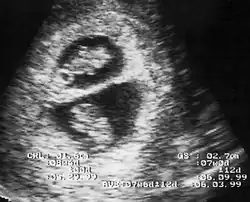

En France, selon les recommandations de la HAS de 2009, révisées en 2016[8], le diagnostic de grossesse gémellaire est effectuée lors de l'échographie du premier trimestre. Cet examen doit déterminer aussi la chorionicité, car elle devient de plus en plus difficile à préciser avec l'évolution de la grossesse. Ce premier examen permet de distinguer les grossesses bichoriales de bon pronostic, et les grossesses monochoriales, plus à risques de complications. Chacun des jumeaux doit être suivi selon les examens réalisés habituellement lors d'une grossesse unique (par exemple : dépistages d'un retard de croissance intra-utérin, d'une trisomie 21, de malformations...)[6].

La fréquence des échographies varie selon le niveau de risques de la grossesse gémellaire, de une par mois à une par semaine. La détermination des risques au dernier trimestre peut influencer le choix de la date d'accouchement[9]